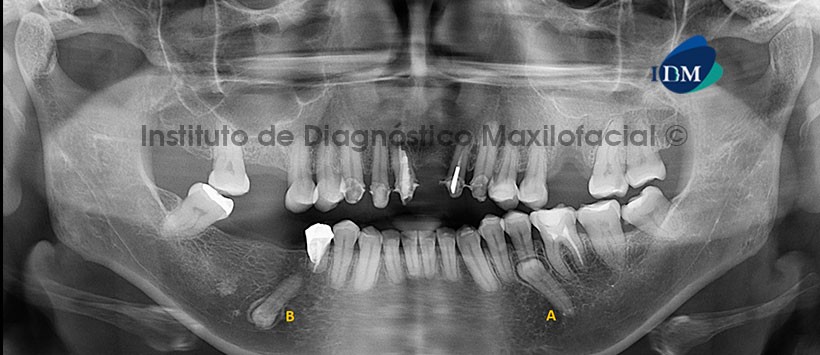

Paciente femenina de 51 años de edad que es referida para el estudio imagenológico previo a la colocación de implantes dentales. A la evaluación de la radiografía panorámica se observa la presencia de dos piezas supernumerarias a las cuales denominaremos A y B. La pieza A se encuentra con la corona proyectada sobre la raíz de la pieza 35 y la pieza B se encuentra proyectada sobre el cuerpo mandibular del lado derecho, a nivel de la región de la pieza 46, en posición invertida y con la corona proyectada sobre el conducto dentario inferior. Así mismo, se evidencia el aplanamiento del contorno del cóndilo mandibular izquierdo, la neumatización alveolar del seno maxilar  derecho, la ausencia de piezas dentarias, múltiples restauraciones coronarias y material de obturación parcial y subextendida de conductos radiculares en algunas piezas dentarias (Fig. 1).

La tomografía computarizada de haz cónico mediante los cortes transaxiales y tangenciales nos muestra la clara relación de las piezas supernumerarias con las estructuras dentarias y óseas colindantes. La corona de la pieza A se encuentra próxima a la tabla ósea lingual y ocasiona el desplazamiento bucal del segmento radicular de la pieza 35. Por otro lado, la corona de la pieza B se encuentra próxima a la tabla ósea lingual y en estrecha relación con el conducto dentario inferior (Fig. 2 y 3).